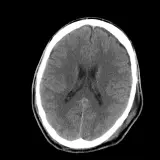

Neuro CT